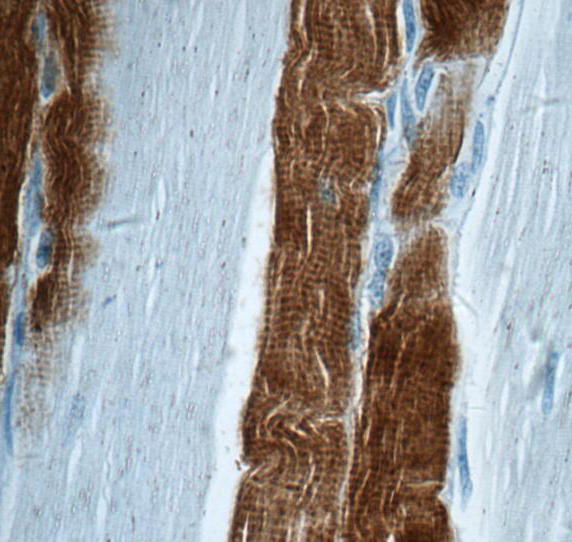

| 验证图片 | Immunohistochemistry of paraffin-embedded human skeletal muscle tissue slide using FNab08839(TNNI2 Antibody) at dilution of 1:50 mouse skeletal muscle tissue were subjected to SDS PAGE followed by western blot with FNab08839(TNNI2 Antibody) at dilution of 1:1000 |